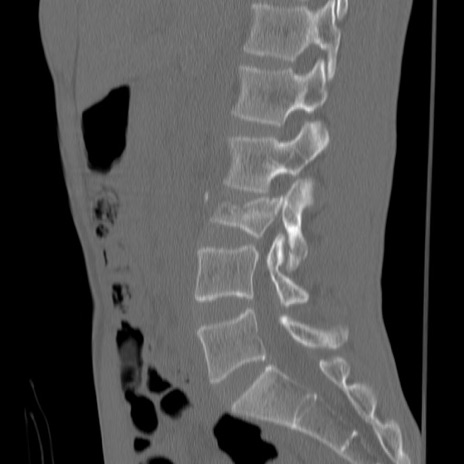

症例3 腰椎CT(矢状断像)

腰椎CT

横断像